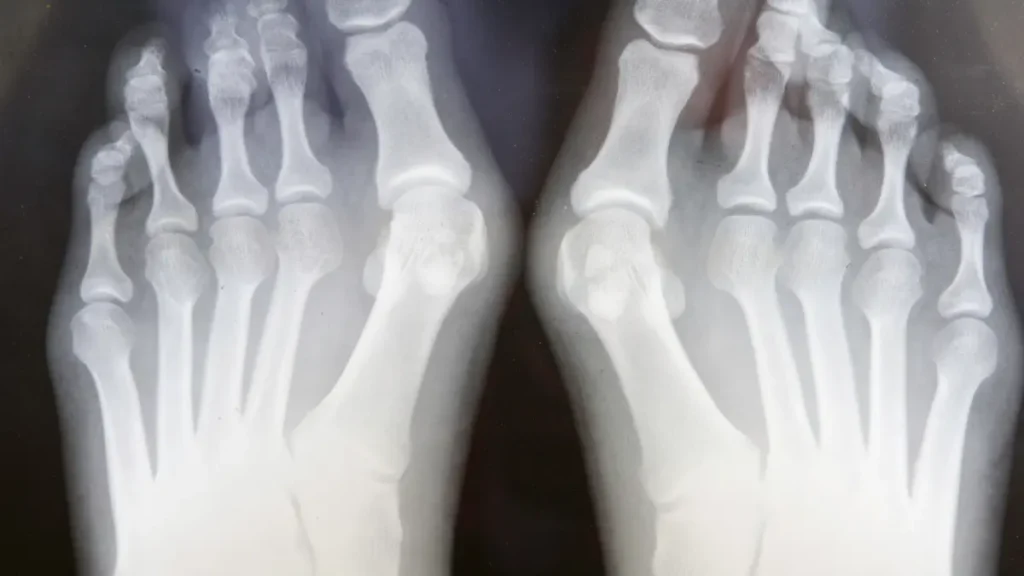

Conforme explicou um especialista em cirurgia minimamente invasiva do joanete, o hálux valgo, conhecido popularmente como joanete, é uma deformidade óssea que ocorre na articulação do dedão do pé. Esta condição causa dor e desconforto, especialmente ao usar calçados.

O tratamento cirúrgico do joanete varia conforme a gravidade e tipo de deformidade. Existem diferentes abordagens cirúrgicas, cada uma com suas indicações específicas.

A cirurgia clássica consiste na abordagem da deformidade por via aberta, utilizando uma incisão de aproximadamente 5cm ao nível da articulação do dedo grande. Isso permite remover o excesso de osso e corrigir a deformidade através de uma osteotomia.

Durante o procedimento, o cirurgião pode realizar uma osteotomia para reposicionar o osso em uma posição mais anatômica. Em casos mais graves, pode ser necessária uma artrodese da articulação.